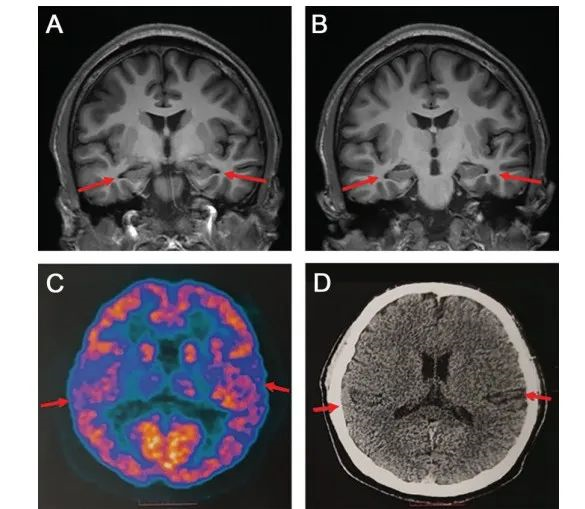

贾龙飞介绍,PET扫描和脑脊液指标检查,以及多种量表检测可以相辅相成,互相印证,以此才可以做出准确的临床诊断。

研究小组对此病例的诊断为“疑似AD”,原因是仍有部分评估结果不符合AD的国际公认诊断标准(NIA-AA)。此外,该文章也提出了此项研究的局限性,由于患者比较年轻,不能接受大脑活检,需要长期随访进一步支持该团队的诊断。